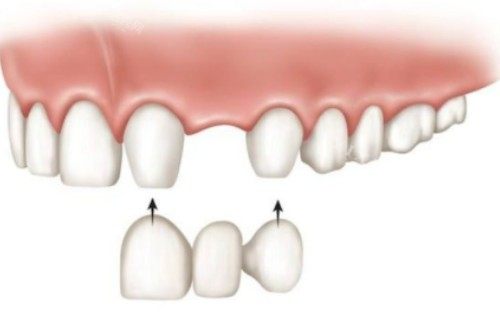

刚走进宁波欣瑞口腔,就感觉环境特别干净整洁,前台的工作人员特别热情,主动问我有什么需求,还很快帮我安排好了医生。给我看牙的是一位经验挺丰富的医生,他先是特别仔细地检查了我缺牙的情况,还耐心地给我讲解镶牙的各种方式,像活动假牙、固定假牙还有种植牙,每种方式的优缺点、价格范围都讲得明明白白。这让我心里有了底,能根据自己的实际情况和经济状况来做选择。

在了解了各种镶牙方式后,我有点拿不定主意。医生看出了我的犹豫,就结合我的口腔条件、日常习惯,给我推荐了适合我的镶牙方案。他说我的牙槽骨条件还不错,比较建议我做种植牙,虽然价格比其他方式贵一些,但是使用起来更接近真牙,也更耐用。医生的正规和负责让我特别放心,我就听从了他的建议,决定做种植牙。

在修养期间,宁波欣瑞口腔的医生还会定期回访我,询问我的修养情况,给我一些指导。大概过了几个月,种植牙就完全修养好了,装上牙冠后,我照镜子一看,简直跟真牙一模一样,而且用起来也特别舒服,吃饭再也不用小心翼翼了。